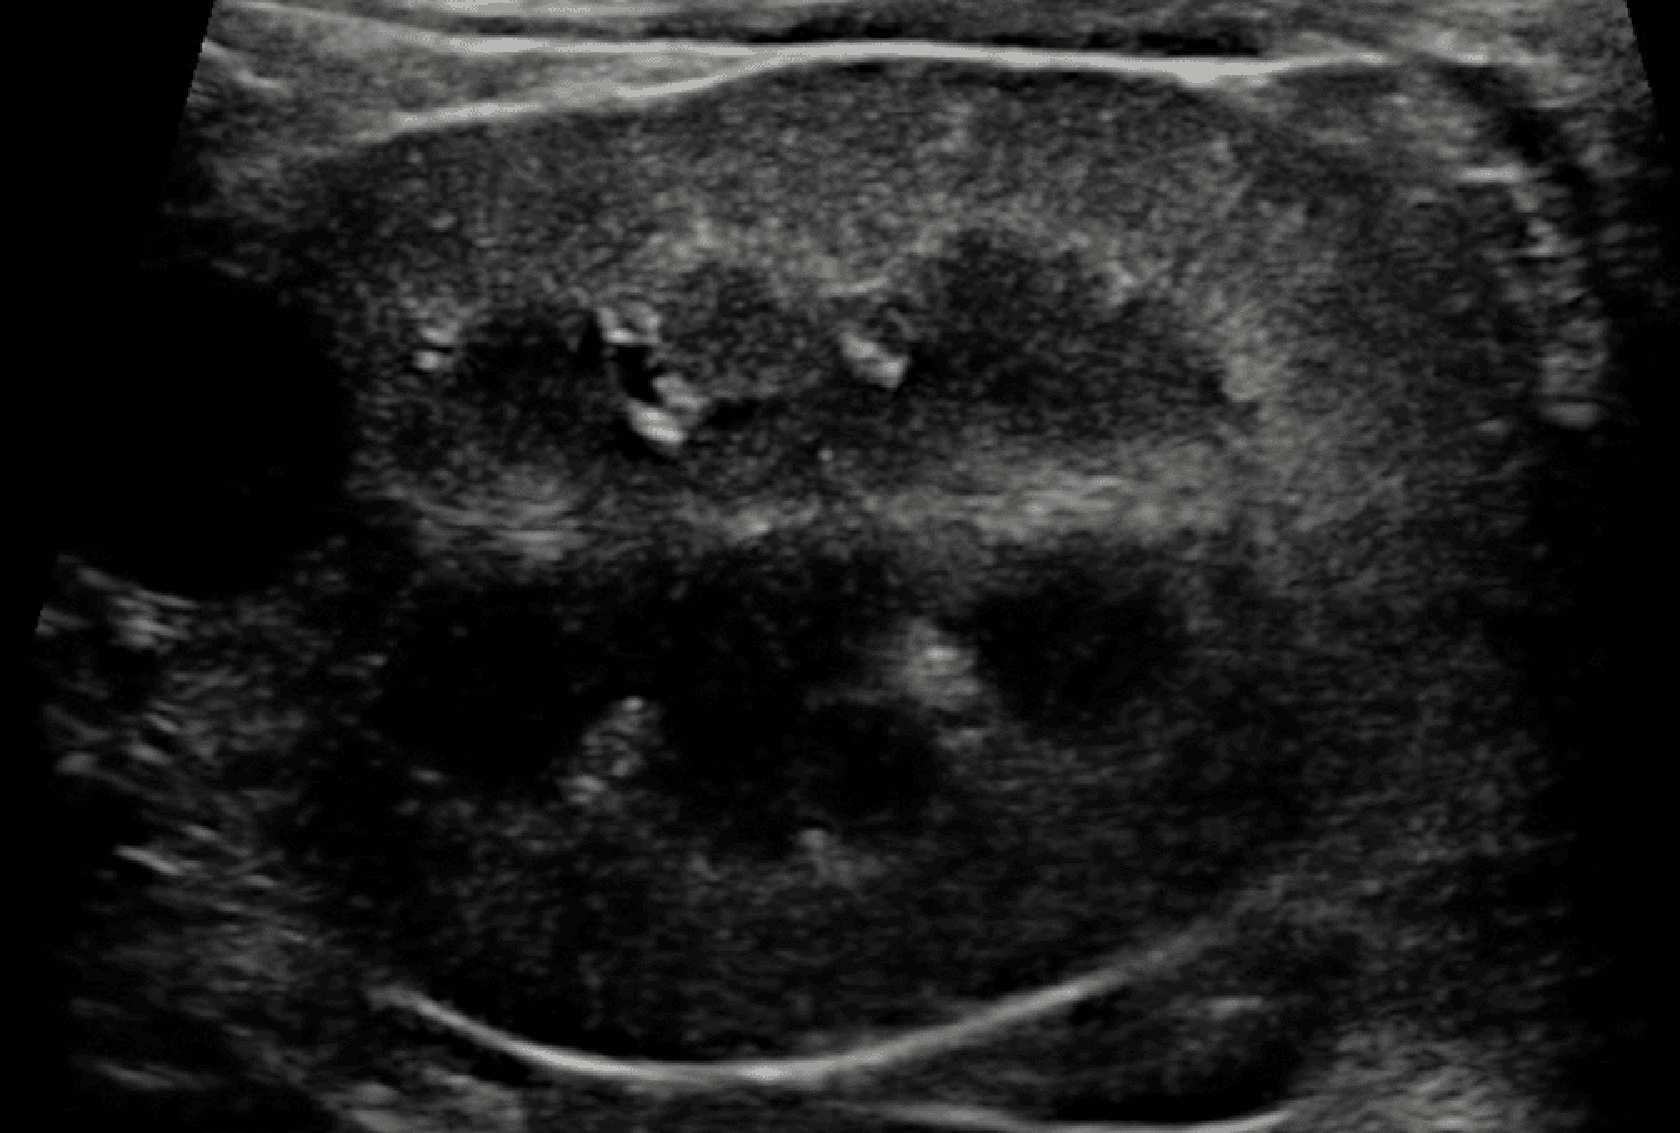

Prawidłowy obraz ultrasonograficzny nerek został szczegółowo omówiony w innych źródłach,7 a poniższy artykuł koncentruje się na przewlekłej chorobie nerek u kotów i psów. Nerki powinny być obrazowane w trzech projekcjach – strzałkowej, dogrzbietowej i poprzecznej (ryc. 1).7 U psów, zwłaszcza małych ras, opisano obecność hiperechogenicznego zewnętrznego pasma rdzeniowego, które obserwuje się z umiarkowaną częstością u pacjentów bez stwierdzonej choroby nerek (ryc. 2).8 U kotów kora nerek może być jednorodnie silnie hiperechogeniczna ze zwiększonym w następstwie zróżnicowaniem korowo-rdzeniowym wtórnym do lipidozy kanalików bliższych (ryc. 3).9 Odkładanie się tłuszczu w kanalikach nerkowych jest konsekwencją otyłości bez jednoczesnego upośledzenia czynności nerek.10 Dodatkowo rutynowo obserwuje się zależny od kąta badania artefaktowy wzrost hiperechogeniczności kory i rdzenia nerek, wtórny do anizotropii, w obszarach, w których kanaliki nerkowe ułożone są prostopadle do płaszczyzny fali ultradźwiękowej. Na przykład podczas obrazowania nerki w projekcji strzałkowej echogeniczność biegunów doczaszkowego i doogonowego będzie ogniskowo i artefaktowo zwiększona (ryc. 4).11 Z doświadczenia autorów wynika, że łagodna nieregularność brzegów nerek, szczególnie u kotów, może być obserwowana w miejscach, gdzie naczynia nerkowe przebiegają wzdłuż torebki nerkowej, i nie powinna być błędnie interpretowana jako zmiana zwyrodnieniowa (ryc. 5). W lokalizowaniu tych naczyń użyteczna jest ultrasonografia dopplerowska kodowana kolorem lub w trybie mocy.

Ryc. 1. Obrazy ultrasonograficzne prawidłowej nerki kota w projekcji: a) strzałkowej, b) dogrzbietowej oraz c) poprzecznej. Towarzyszące ilustracje przedstawiają przebieg płaszczyzn obrazowania.